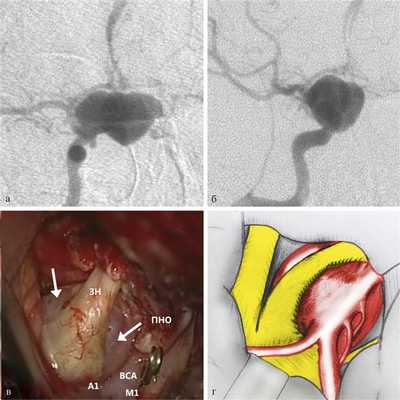

Медиальные аневризмы — самая многочисленная группа, составившая 41,5% от всех аневризм, включенных в исследование. Шейка таких аневризм локализуется в области медиальной стенки ВСА. Распространяясь в супраселлярную область, они могут имитировать опухоли данной локализации (аденому гипофиза, менингиому бугорка турецкого седла). В редких случаях такие аневризмы могут вызывать гормональные нарушения, связанные с компрессией стебля гипофиза (несахарный диабет). Отличительным хирургическим признаком служит то, что купол медиальной параклиноидной аневризмы всегда расположен под зрительным нервом, грубо деформируя его и хиазму, в связи с чем для клинической картины наиболее характерны зрительные нарушения. Для выключения аневризмы требуются ее диссекция от зрительного нерва, декомпрессия крыши канала зрительного нерва и резекция ПНО. Клипирование таких аневризм чаще производится стандартными клипсами (прямыми, изогнутыми), которые накладываются вдоль медиальной стенки ВСА (рис. 3).

Рис. 3. Параклиноидная аневризма медиального расположения. а — ЦАГ, прямая проекция; б — ЦАГ, боковая проекция; в - операционный вид (ЗН ‒ зрительный нерв, ПНО — передний наклоненный отросток, ВСА — внутренняя сонная артерия; стрелками обозначено тело аневризмы); г — схема операционной картины: зрительный нерв и хиазма перерастянуты и смещены вперед, купол аневризмы распространяется под зрительный нерв.